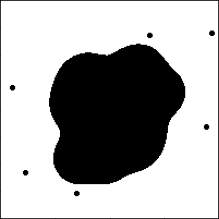

4.1 Application to Lung Adenocarcinoma Pathology Images

Lung cancer is one of the most deadly cancers (Siegel, Miller and Jemal, 2020). One of the most common types of lung cancer is adenocarcinoma which accounts for about 40% of all lung cancers (Zappa and Mousa, 2016) and has various morphological features (Matsuda and Machii, 2015). We use 230 pathology images of 133 lung adenocarcinoma patients in the National Lung Screening Trial (NLST) data. All images are obtained under 40X magnification, and the median size of images is 24,24419,261 pixels. The image patches of size 300300 pixels (7575 microns) are segmented into three classes of the tumor, normal, and empty regions using a deep convolutional neural network (CNN) (Wang et al., 2018). For example, for a given NLST pathology image of size 30,00030,000, the CNN model generates the segmented image of size 100100. We implement an additional pre-processing step to remove noise: a single pixel is considered to be noise when its class is different from the surrounding eight singular-class pixels, and the noise pixels are reclassified to the class of the surrounding pixels. The denoised three-class images are transformed using the SEDT-3. Figure 5 presents the pathology image, the segmented three-class image of Wang et al. (2018), and the SEDT-3 image.

A sequence of cubical complices is constructed using the SEDT-3 values as filtration, and persistent homology is computed using GUDHI (Dlotko, 2015). We replace the dimension-zero result with infinite death value with and exclude the dimension-one result with infinite death value to remove features related to empty regions. The median number of the computed features per image slice is 694 for dimension-zero and 1,768 for dimension-one. The ranges of persistence diagrams are for dimension-zero and for dimension-one. The smoothing parameters and are used for the persistence surface functions.

Table 1 shows the results of the CoxPH and FCoxPH models. The clinical variables behave similarly for both models except for the tumor size. The p-value of the tumor size variable increases in the FCoxPH model as the functional predictors are added, suggesting that one of the functional predictors may include the tumor size information. The p-values of the Wald tests are close to zero for both models.

Figure 6 shows the estimated functional coefficients. The dimension-zero topological features summarized in the blue-colored areas in quadrants II and III of Figure 6(a) correspond to the aggressive tumor patterns. First, the colored area in quadrant II in Figure 6(a) represents the small-sized scattered tumor regions close to each other (e.g., D of Figure 2(a)). Also, quadrant III of Figure 6(a) represents the relatively small connected tumor shapes. The small connected tumor features are spotted where multiple tumor regions spread inside normal regions (e.g., H of Figure 2(a)). These patterns imply a fast spread of tumors.

On the other hand, the shapes that appear in the red-colored regions in quadrant I of Figure 6(b) match with less aggressive tumor patterns. The red-colored region corresponds to broken-ring-shaped tumor regions (i.e., see the examples of areas N, P, and O in Figure 2(b)). These shapes require an ample-sized normal region that could be surrounded by the tumor but not invaded by the tumor.

These dimension-one features do not appear when small tumor regions penetrate the normal region inside the broken-ring-shaped tumor regions. Therefore, the broken-ring-shaped tumor may not likely appear where the small tumor regions are densely populated. These results coincide with the findings that tumor shape complexity and heterogeneous spread are associated with prognosis (Yokoyama et al., 1991; Miller et al., 2003; Chatzistamou et al., 2010; Vogl et al., 2013; Grove et al., 2015) and tissue transport properties (Soltani and Chen, 2012; Sefidgar et al., 2014).

Another interesting observation is that the relatively small-sized topological features, approximately a radius of up to pixels ( microns), have a strong association with the hazard function. We see that the estimated non-zero functional coefficients, the colored regions in Figure 6, are close to the origin compared to the ranges of persistence surface functions. The topological features near the origin correspond to small-sized features that have small birth and death values. This indicates that the valuable information for our lung cancer study obtained by the proposed persistent homology approach relates mainly to local shapes and patterns.